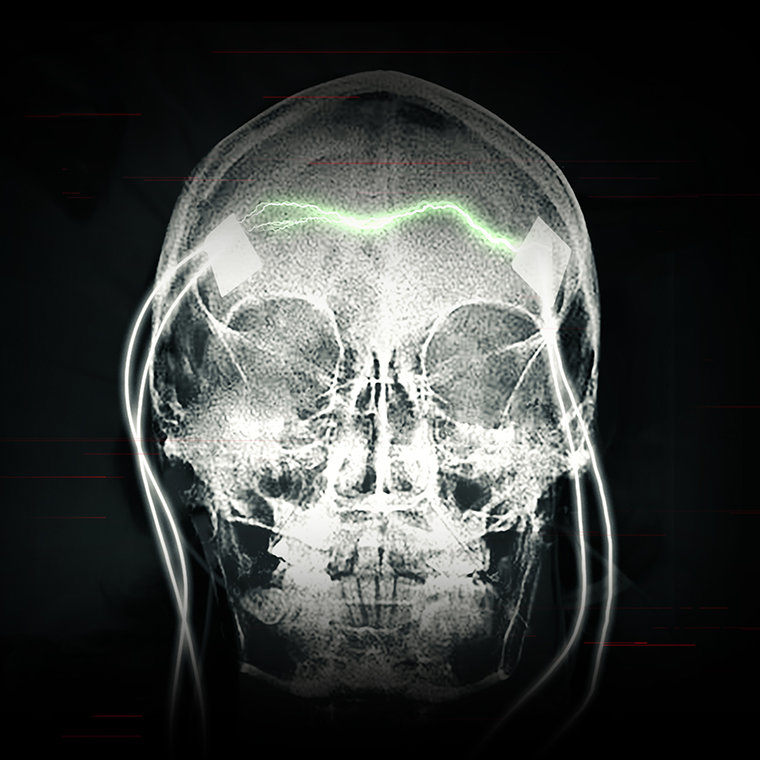

À présent, les psychiatres agressent habituellement le cerveau avec bien plus d’électricité qu’auparavant, afin de provoquer une crise d’épilepsie.

Le résultat reste le même : une crise de type grand mal, et des lésions cérébrales qui peuvent être permanentes. Aujourd’hui, le courant considérablement plus élevé peut créer des trous dans les cellules du cerveau et les détruire. L’électricité peut aussi détruire les cellules en produisant de la chaleur. L’IRM effectuée sur des patients victimes d’ECT, a révélé la présence de cicatrices et d’un rétrécissement du cerveau – preuve irréfutable de graves lésions.